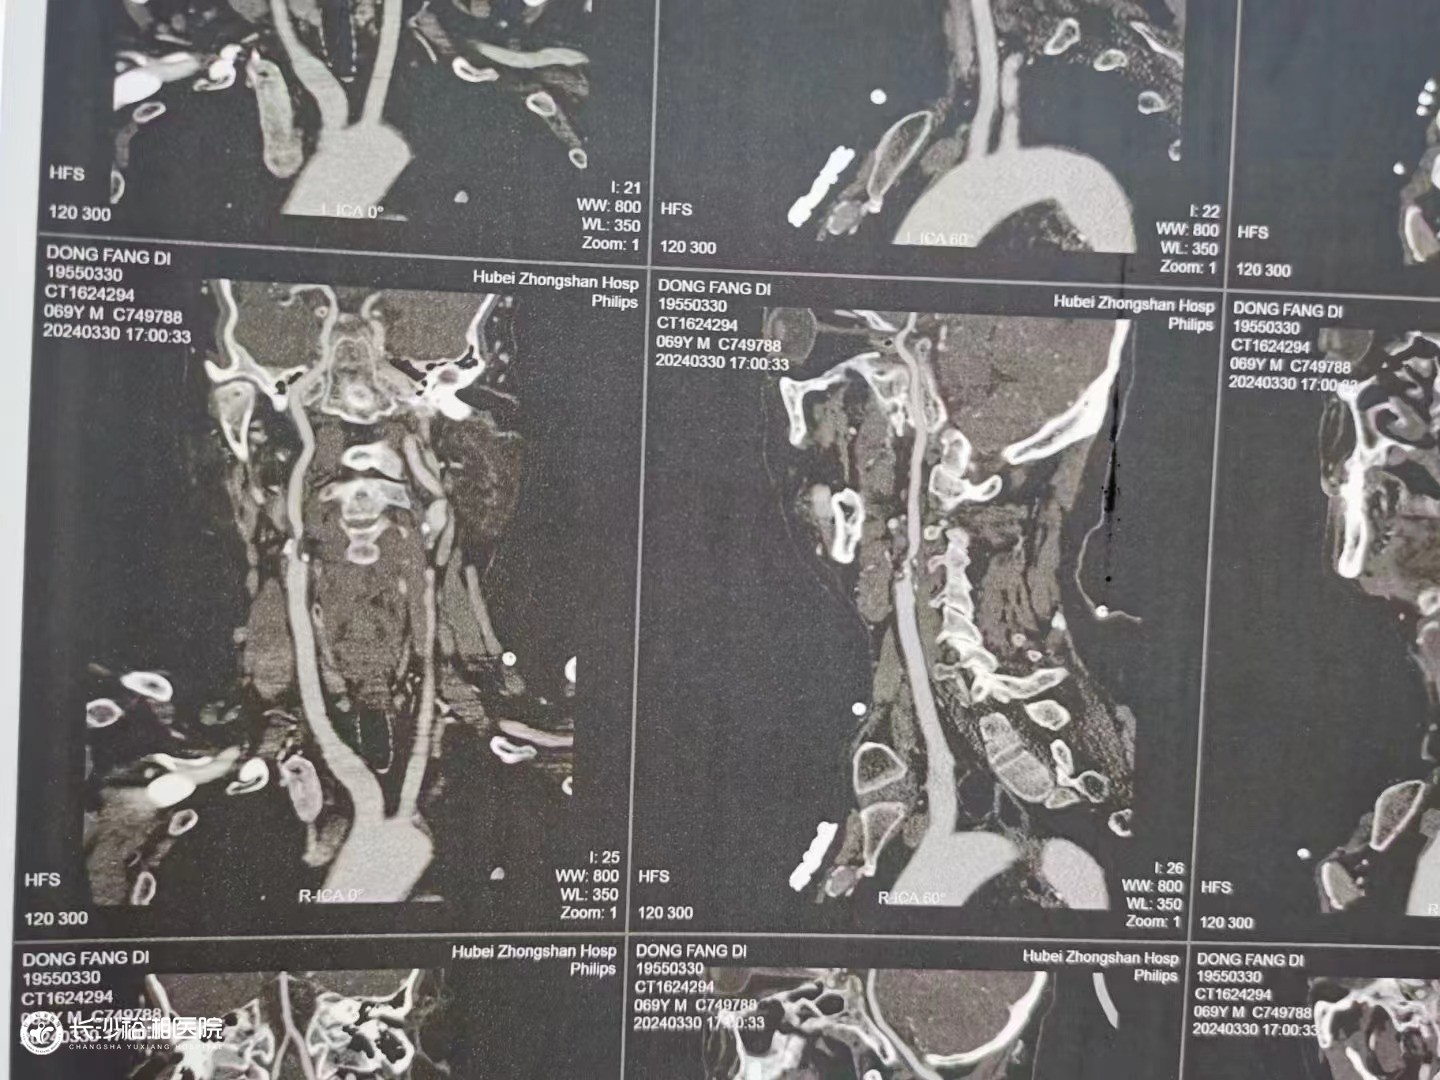

頸動(dòng)脈粥樣硬化斑塊切除術(shù)

腦卒中是我國(guó)城鄉(xiāng)居民死亡和殘疾的最主要原因,而頸動(dòng)脈狹窄是導(dǎo)致腦卒中的重要因素。頸動(dòng)脈狹窄的治療包括頸動(dòng)脈粥樣硬化斑塊切除術(shù)(CEA)、頸動(dòng)脈支架成形術(shù)(CAS)和藥物治療等。CEA被公認(rèn)是頸動(dòng)脈狹窄治療的金標(biāo)準(zhǔn),可以清除堵塞血管的增生斑塊,改善腦供血,顯著降低潰瘍型斑塊栓子脫落導(dǎo)致腦梗死的風(fēng)險(xiǎn),而且無植入物,手術(shù)費(fèi)用低,療效肯定。